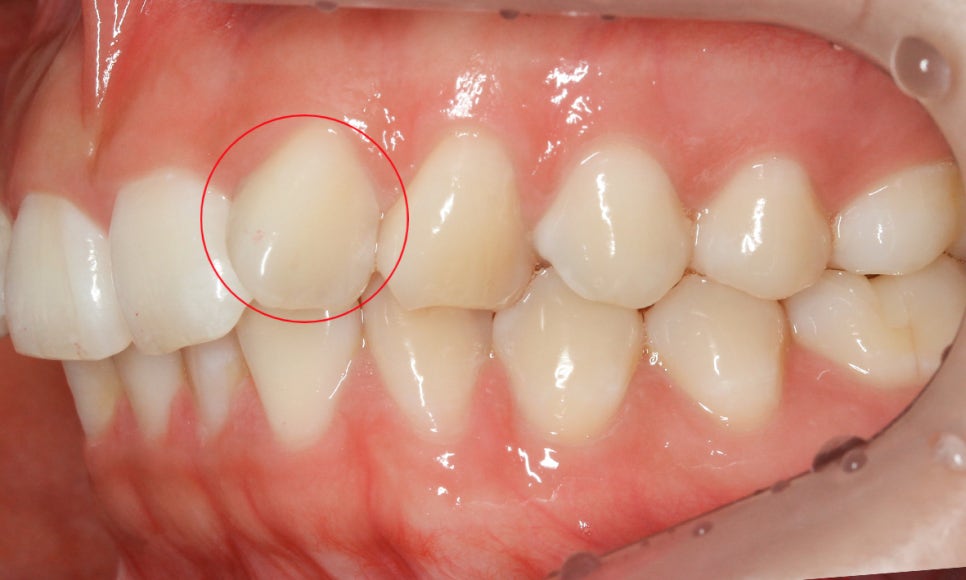

교정 전 정밀진단 1차

세라믹교정 전 정밀진단을 통해

치아의 상태를 확인한 결과

상악 측절치의 각도가 약 90도 가량

틀어져 있는 것을 확인하였습니다.

정면에서는 보이는 것 처럼

치아의 앞면이 아닌 측면이 보이는 모습으로

이러한 앞니틀어짐 증상을 흔히 덧니라고

오인하고 내원하시는 분들이 많은데요

덧니와 앞니틀어짐을 구분하는 방법은

잇몸라인과 치아가 맹출된 높이를

확인하시면 쉽게 파악하실 수 있습니다.

위의 앞니 틀어짐 case의 경우

상악 측절치가 맹출된 높이를 보시면

치아의 각도를 제외하고 주변 치열과

크게 이질적인 느낌은 들지 않는데요,

잇몸 라인도 일정하게 구치부까지

이어지는 모습으로 해당 치아는

덧니라고 보기에는 어려움이 있습니다.